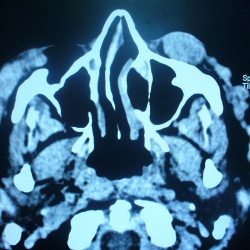

Здравствуйте,уважаемые доктора!!!.При описании ППН у детей,всегда испытываю трудности.То ли пазухи еще не развиты,то ли затемнены.Вот два варианта : первый снимок-ребенок 3г,второй-8 лет.В обоих...